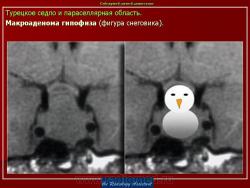

Патология области турецкого седла.